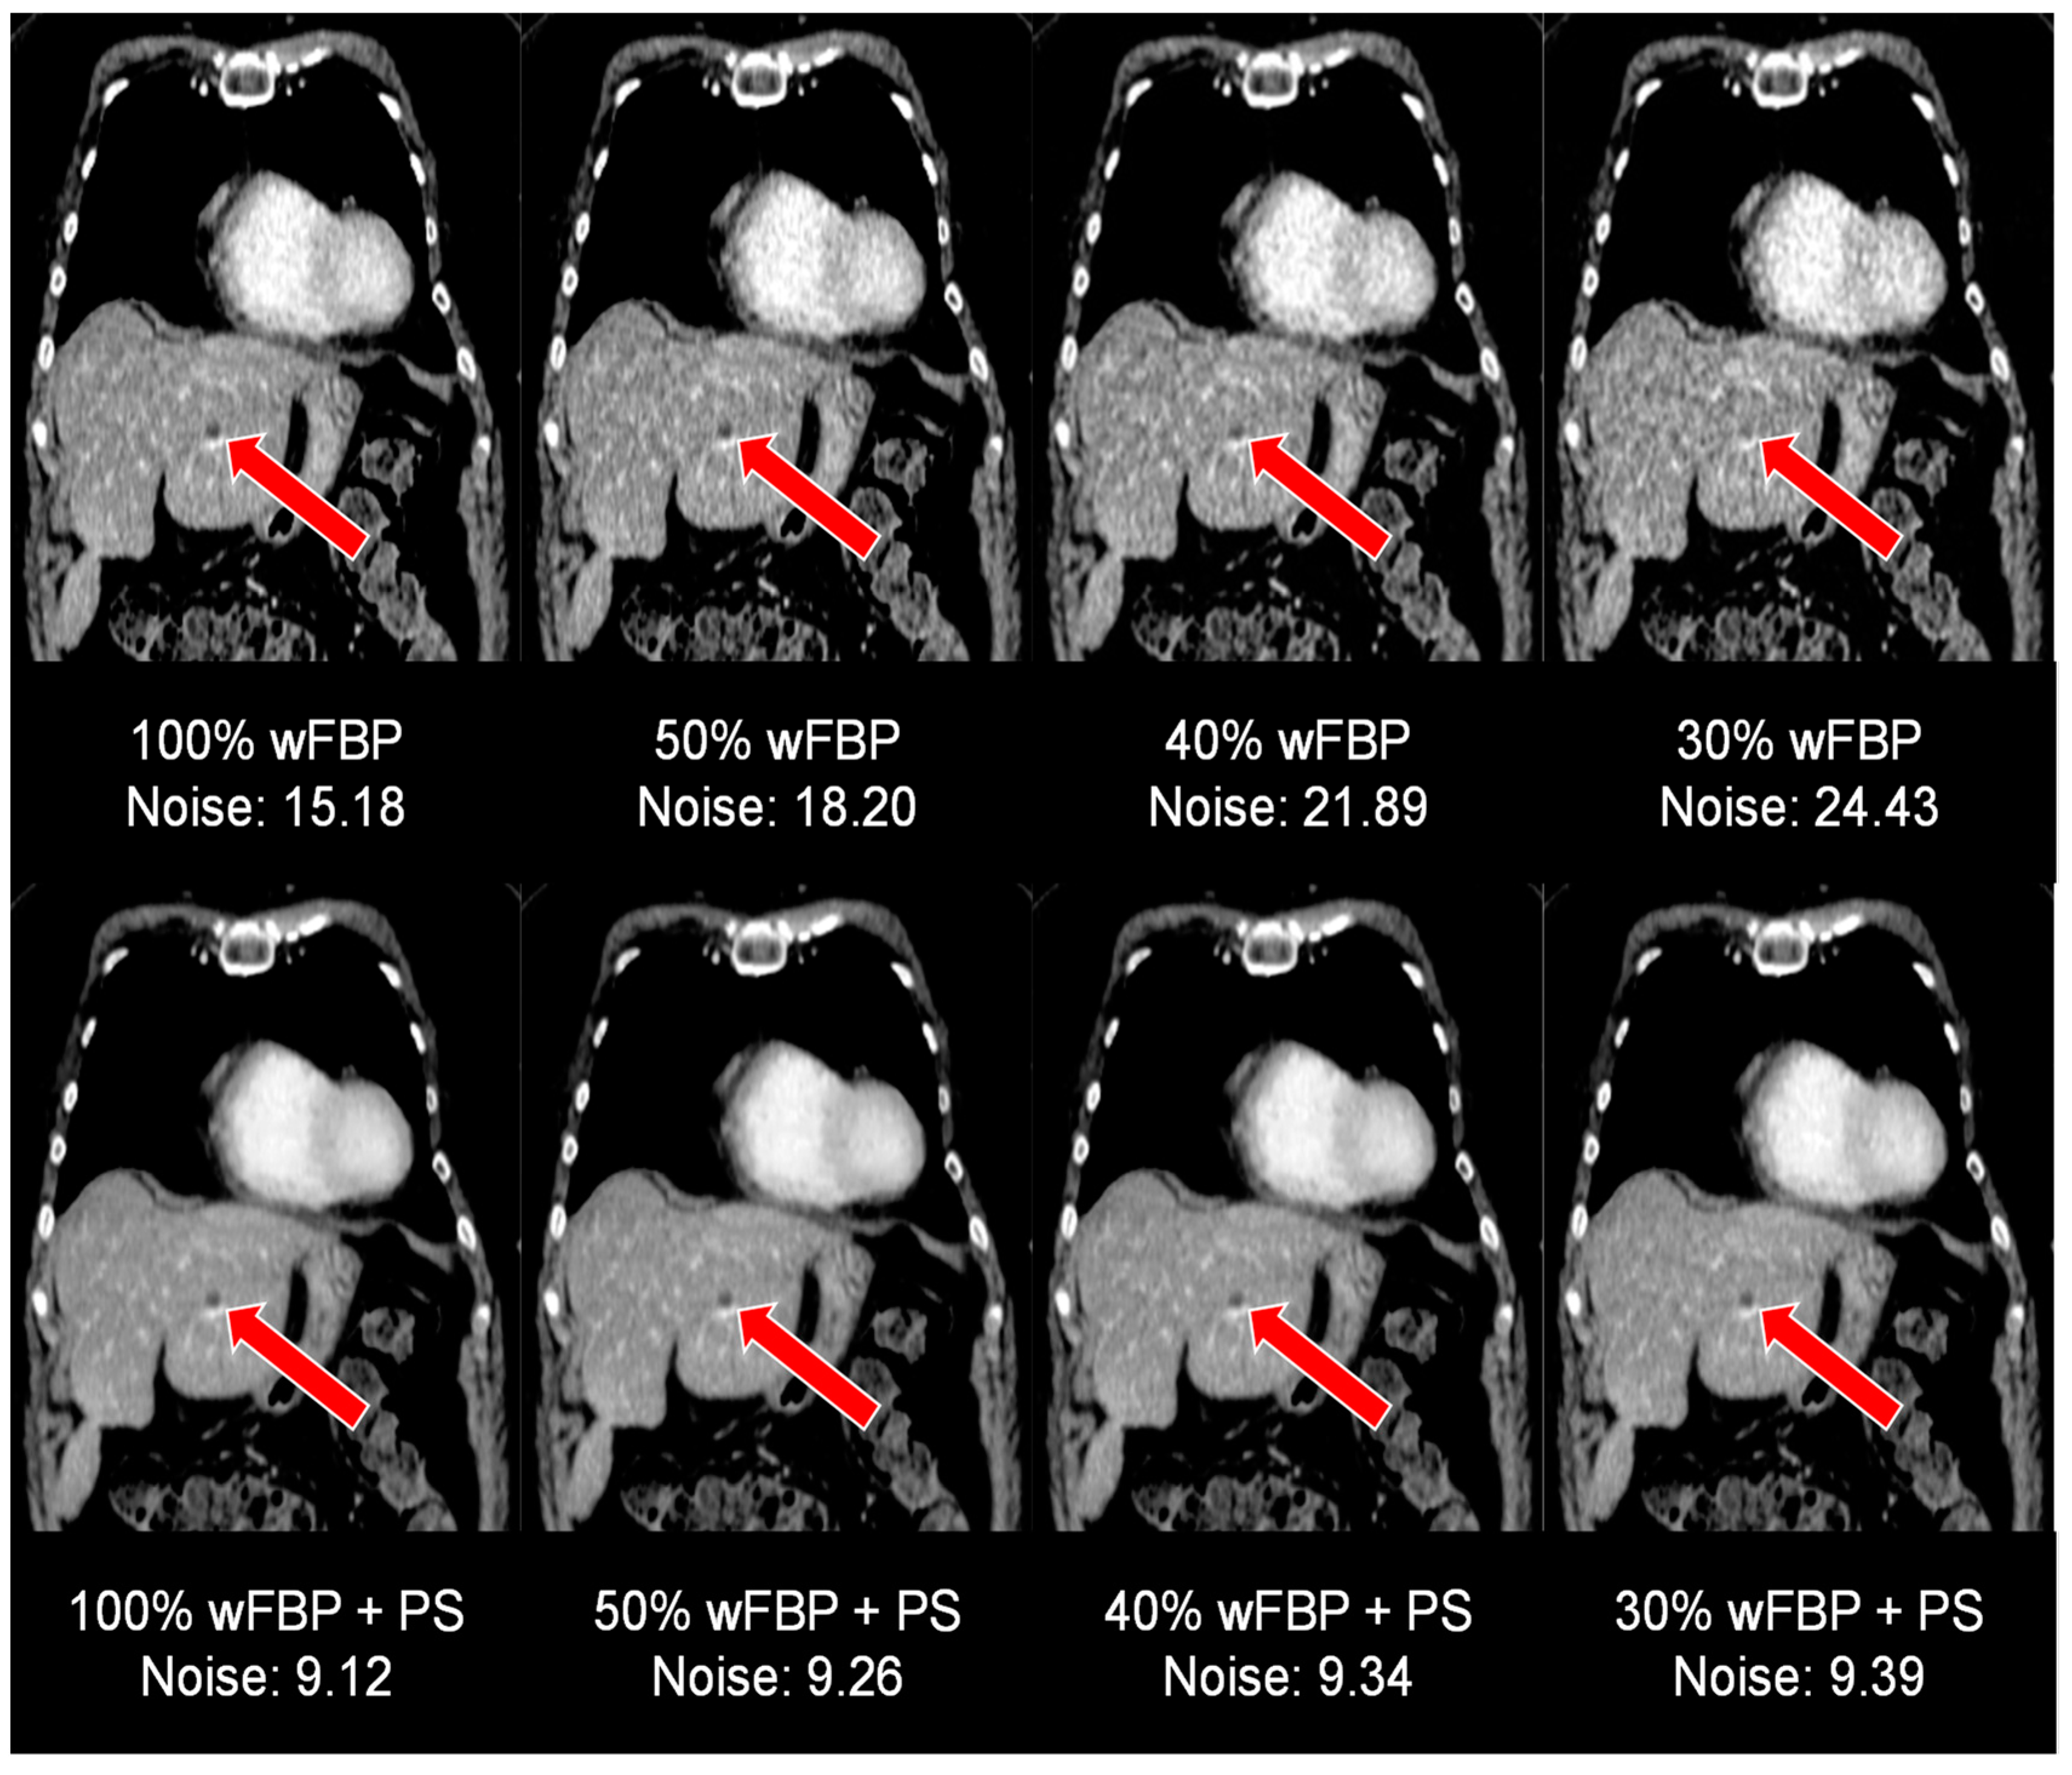

| Noise | p (Two-Sided, Adjusted) vs. 100% ED | ||||||

|---|---|---|---|---|---|---|---|

| ED | Mode | Mean ± SD | wFBP | ADMIRE 2 | wFBP + PS | ADMIRE 2 + PS | |

| SOMATOM Definition AS+ | 100% | wFBP | 12.85 ± 1.63 | <0.001 | <0.001 | <0.001 | |

| ADMIRE 2 | 10.75 ± 1.36 | <0.001 | <0.001 | <0.001 | |||

| wFBP + PS | 7.8 ± 0.13 | <0.001 | <0.001 | 0.423 | |||

| ADMIRE 2 + PS | 7.8 ± 0.13 | <0.001 | <0.001 | 0.423 | |||

| 50% | wFBP | 17.99 ± 2.51 | <0.001 | <0.001 | <0.001 | <0.001 | |

| ADMIRE 2 | 15.05 ± 2.11 | <0.001 | <0.001 | <0.001 | <0.001 | ||

| wFBP + PS | 7.8 ± 0.15 | <0.001 | <0.001 | 0.936 | 0.943 | ||

| ADMIRE 2 + PS | 7.8 ± 0.15 | <0.001 | <0.001 | 0.860 | 0.991 | ||

| 40% | wFBP | 20.06 ± 2.89 | <0.001 | <0.001 | <0.001 | <0.001 | |

| ADMIRE 2 | 16.78 ± 2.42 | <0.001 | <0.001 | <0.001 | <0.001 | ||

| wFBP + PS | 7.8 ± 0.18 | <0.001 | <0.001 | 0.947 | 0.941 | ||

| ADMIRE 2 + PS | 7.8 ± 0.17 | <0.001 | <0.001 | 0.963 | 0.969 | ||

| 30% | wFBP | 23.07 ± 3.46 | <0.001 | <0.001 | <0.001 | <0.001 | |

| ADMIRE 2 | 19.29 ± 2.89 | <0.001 | <0.001 | <0.001 | <0.001 | ||

| wFBP + PS | 7.8 ± 0.2 | <0.001 | <0.001 | 0.980 | 0.981 | ||

| ADMIRE 2 + PS | 7.8 ± 0.2 | <0.001 | <0.001 | 0.979 | 0.969 | ||